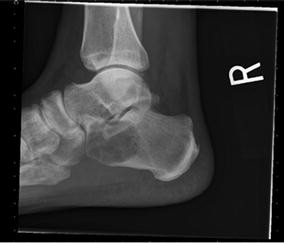

A 60-year-old male was evaluated for insidious onset of right foot pain over 4 months, made worse by walking and standing. Radiographs at an outside facility were reportedly normal. Two corticosteroid injections into the sinus tarsus provided no relief. Upon referral new radiographs were obtained (Fig. 1). Magnetic resonance imaging (MRI) showed a complex lesion in the anterior calcaneus with some surrounding edema and potential concern for cortical disruption (Figs. 2, 3). A computed tomography (CT) guided biopsy of the cyst showed a lytic destructive lesion within the central and anterior process of the calcaneus. There was cortical destruction along multiple sites at the margins of the lesion and slight scattered calcifications (Fig. 4). The pathologic report revealed cords and clusters of epithelioid cells and foci of spindle cells in a myxochondroid matrix (Figs. 5, 6). Some of the epithelioid cells contained vacuoles and rare erythrocyte (Fig. 7). Immunohistochemical stains identified CD31, CD34, and CAMTA1 (Figs. 8, 9). Mixed cytokeratin stain (MCK) showed very focal and equivocal staining and D2-40 and epithelial membrane antigen (EMA) were negative. There was extensive necrosis and some spindling but no invasion of the surrounding bone. These findings supported a diagnosis of epithelioid hemangioendothelioma.